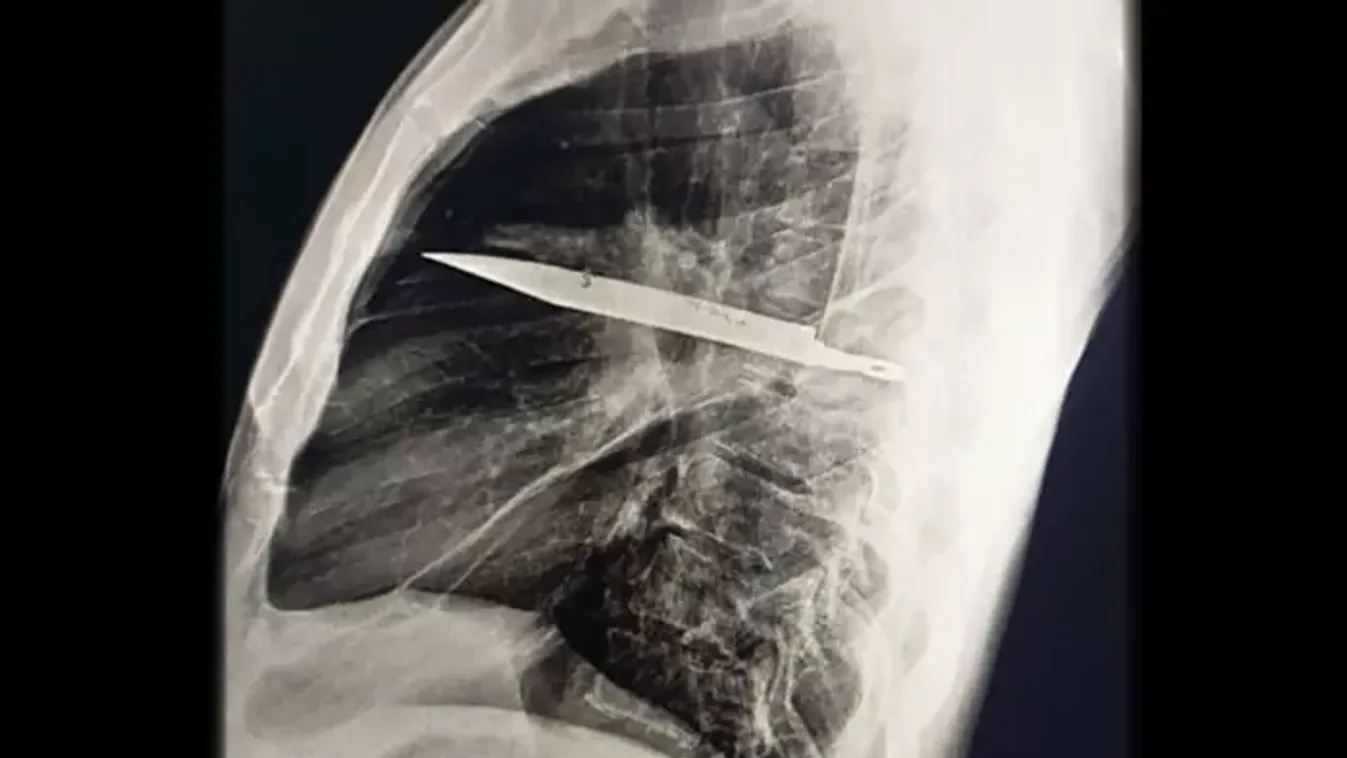

Csak akkor figyeltek fel rá, amikor genny kezdett szivárogni a testből.